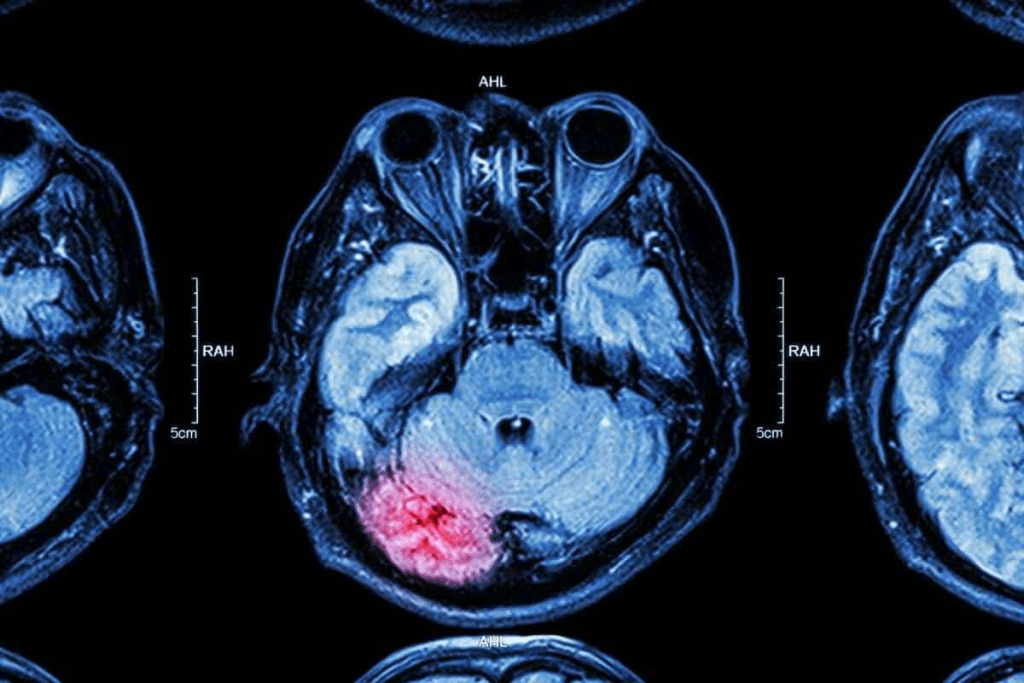

Brain cancer scans use advanced imaging to find and show tumors. These techniques are key for spotting abnormal tissue and seeing how big tumors are.

How Medical Imaging Detects Abnormal Tissue

CT and MRI scans find abnormal tissue in different ways. CT scans use X-rays to make detailed brain images, showing where things are off. MRI uses magnetic fields and radio waves for clear images of soft tissues, helping spot brain tumors.

Experts say MRI is better than CT for finding some brain tumors, like small ones or those in hard-to-see spots.

Contrast agents make tumors easier to see during scans. These substances, like gadolinium for MRI or iodine for CT, are given to patients before scanning. They highlight abnormal tissue, helping doctors see tumors more clearly.

This clear view helps doctors make accurate diagnoses and plan treatments. Medical experts say contrast agents make imaging better, helping doctors see tumors more precisely.